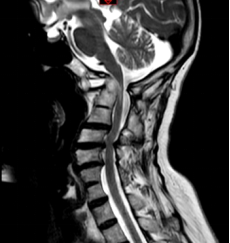

陈阿婆家属慕名来到仁济医院咨询,脊柱外科行政副主任、主任医师朱超接诊后,对陈阿婆的影像学资料进行了详细分析,发现她属于罕见的上颈椎“三明治”畸形,寰椎枕骨化合并Klippel-Feil(颈椎分节不全)畸形,同时有重度倾斜型侧块关节,复位难度大。

寰枢椎脱位,脊髓受压严重

朱超主任介绍,上颈椎又称寰枢椎,指第一、二颈椎,是连接大脑与躯干的关键部位,其结构复杂、活动灵活,承担着支撑头部、保护神经及血管的重要使命。由于发育、炎症、外伤等多种因素,寰枢关节可能发生脱位,导致脊髓神经受压,患者可出现神经元损害的表现,严重时可出现高位截瘫。由于该区域解剖结构复杂,手术难度大、风险高,稍有不慎可能损伤椎动脉、脊髓等重要结构,导致出血、瘫痪乃至死亡等灾难性后果。进一步检查发现,陈阿婆的椎动脉迂曲、变异,走行在侧块的正后方,还要在增生的瘢痕区域进行手术,继发损伤的风险极高。